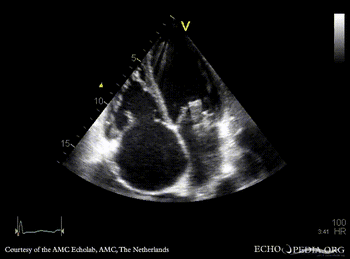

Severe prolaps of PMVL

PLAX: prolaps of PMVL, huge amount of pleural effusion PLAX: Color Doppler, severe mitral regurgitation, excentric jet